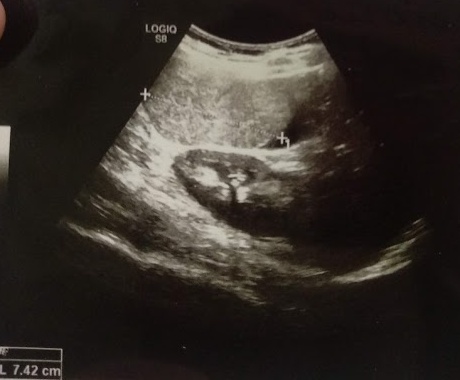

Обязательным при удалении больших гемангиом для предупреждения массивного кровотечения из питающих сосудов и прилегающих печеночных вен является наложение турникета на гепатодуоденальную связку (прием Прингла), что применено нами при правосторонних гемигепатэктомиях и сегментэктомиях правой доли (n = 15). Для уменьшения интраоперационной кровопотери до операции в 3 (10,00 %) случаях произведена успешная селективная РЭО ветвей печеночной артерии, питающих опухоль (рис. 3).

Рис. 3. Гемангиома правой доли печени. Состояние после РЭО ветвей правой печеночной артерии. Интраоперационное фото